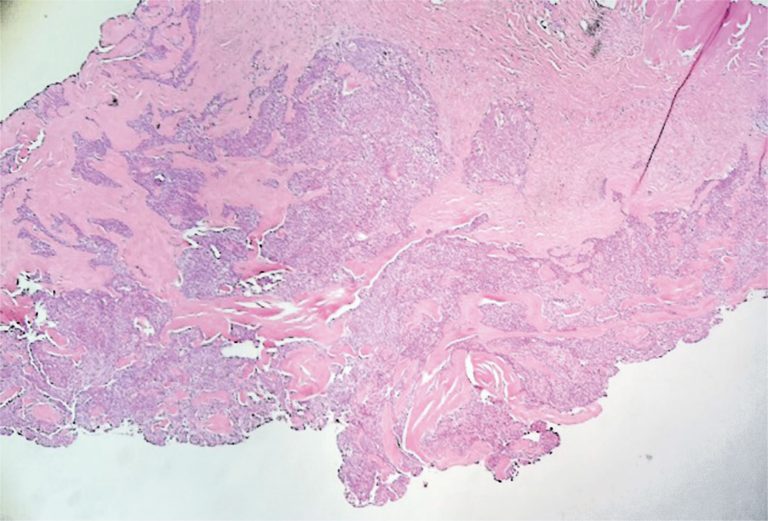

ABSTRACT The etiologies of vulvar nodules range from infectious to neoplastic. Owing to the wide spectrum of vulvar diseases, clinical differentiation of the lesions is crucial for adequate diagnosis and management. A 46-year-old patient presented with a nodular lesion in the vulvar region that had been growing slowly for 10 years. Gynecological examination revealed the presence of a solid nodular lesion measuring approximately 3 cm in the middle third of the right labia majora without phlogistic signs or secretion discharge. […]